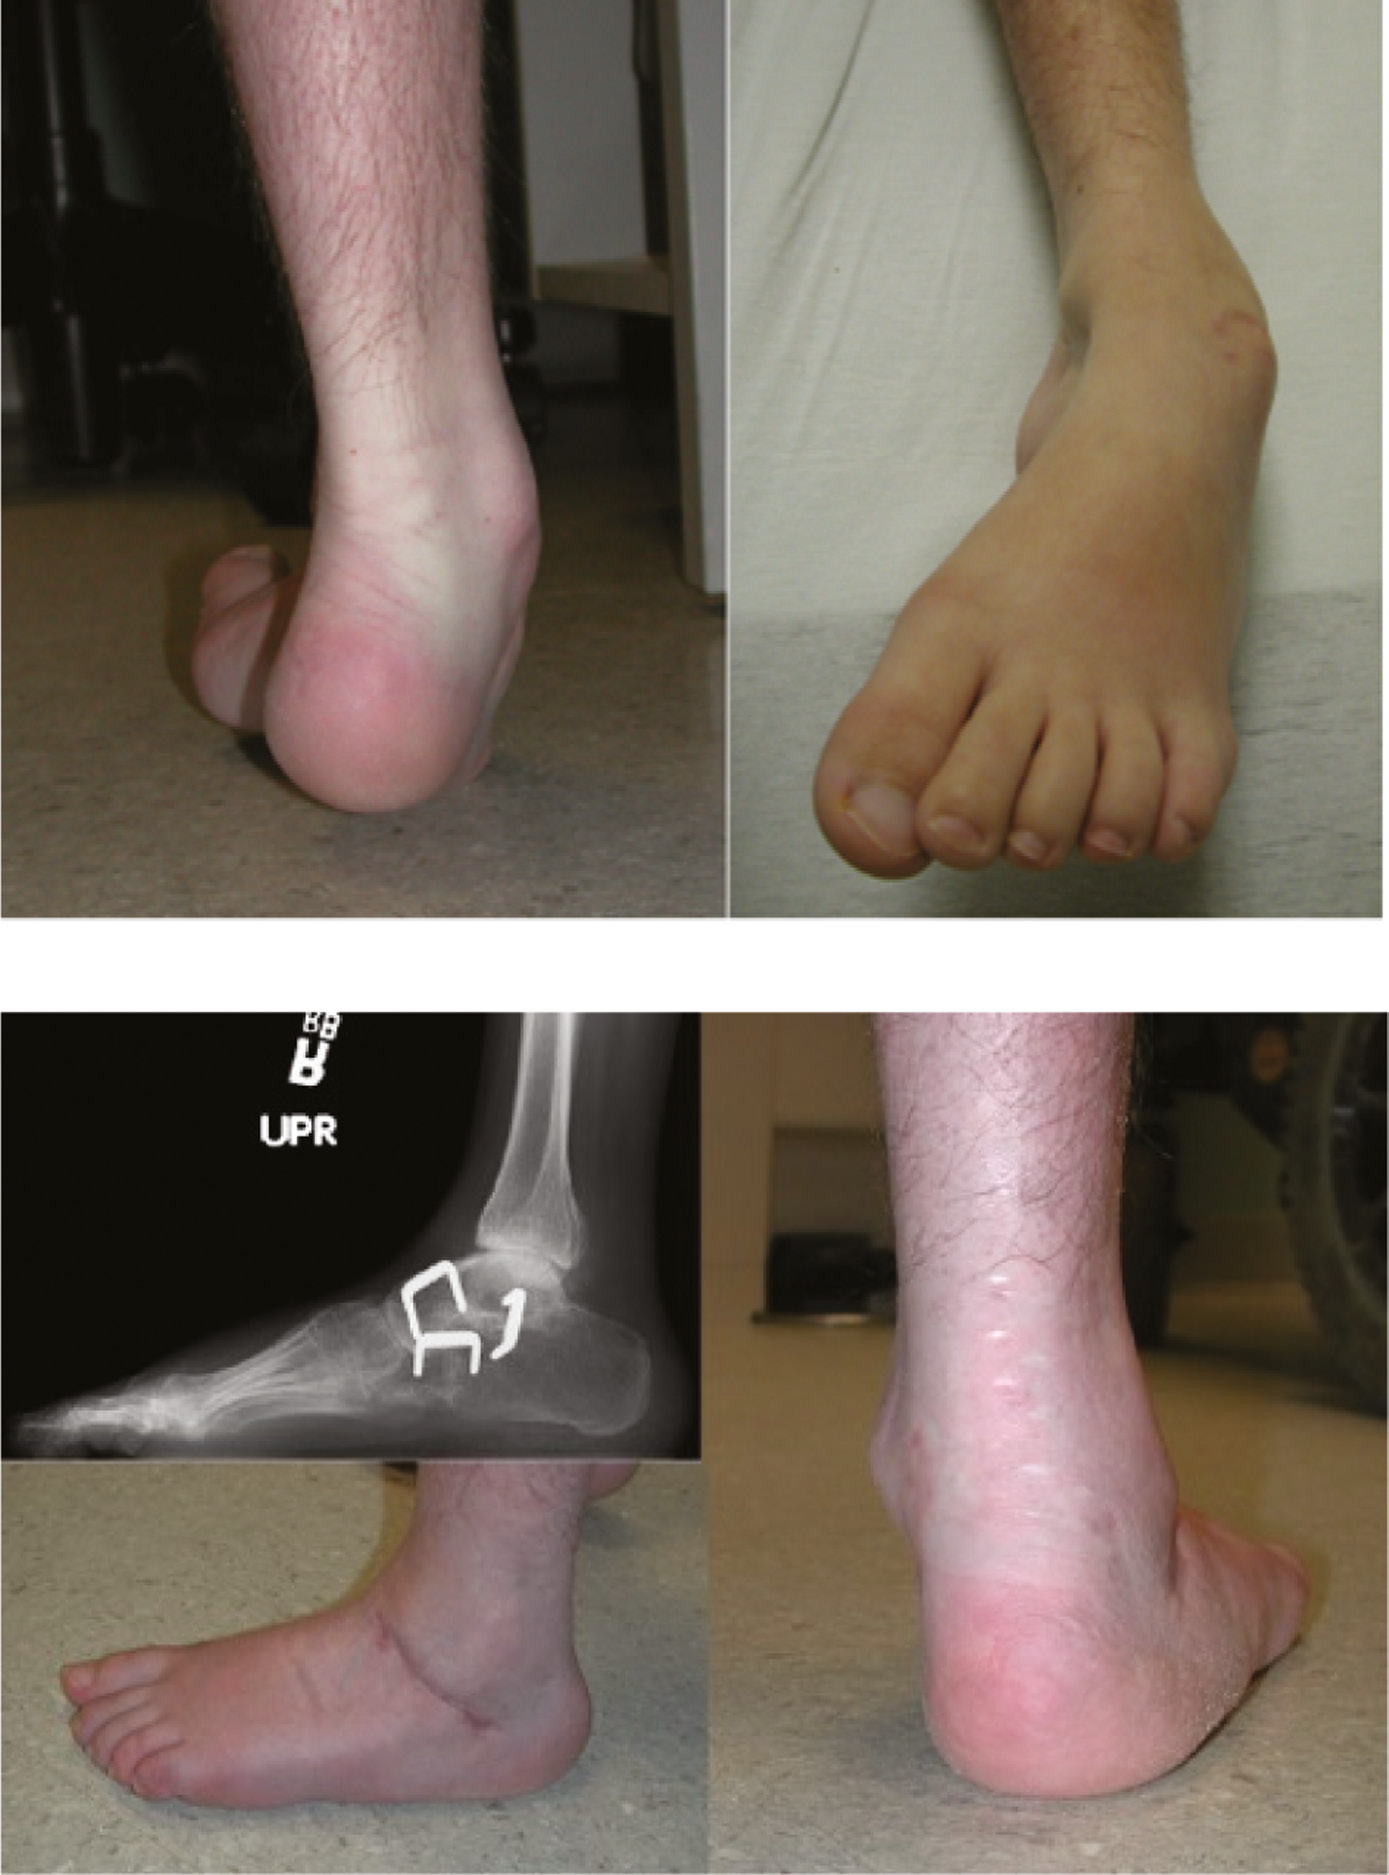

Figure 4. This boy with a syrinx has a unilateral cavovarus foot deformity (top) with claw toes (bottom).

jposna20220035_fig4.jpg